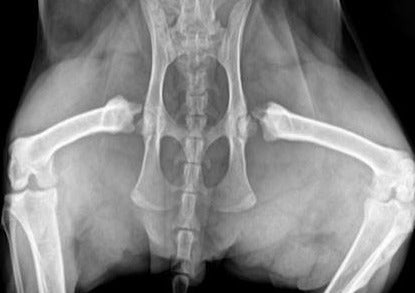

The limping cat presents a unique challenge to clinicians. Although most patients that present to orthopedic surgeons are dogs, cats are prone to many of the same conditions but they may not be treated in the same manner. This lecture will cover a range of orthopedic diseases that are commonly seen in cats as well as review differences in anatomy and physical examination when compared to dogs. Conditions covered will include capital physeal fractures, patella luxation, cranial cruciate ligament rupture, synovial osteochondromatosis, Achilles tendon rupture, fractures, and luxations. Surgical treatment and post-operative care will also be reviewed with emphasis on differences between the species.